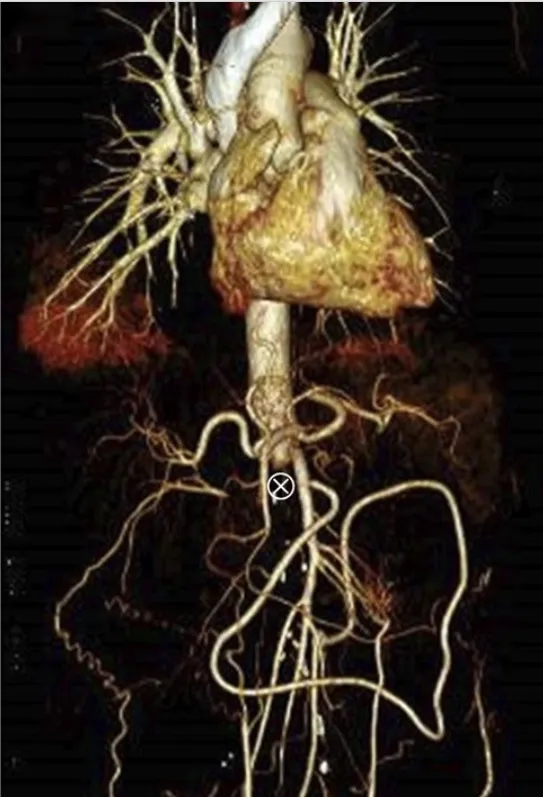

¡Atención al uso prolongado de Nitrofurantoína en ITU recurrente!

¡Atención al uso prolongado de Nitrofurantoína en ITU recurrente!

Siempre debemos prestar atención a los efectos secundarios de los medicamentos más comúnmente utilizados. ¡Echa un vistazo a este caso clínico!